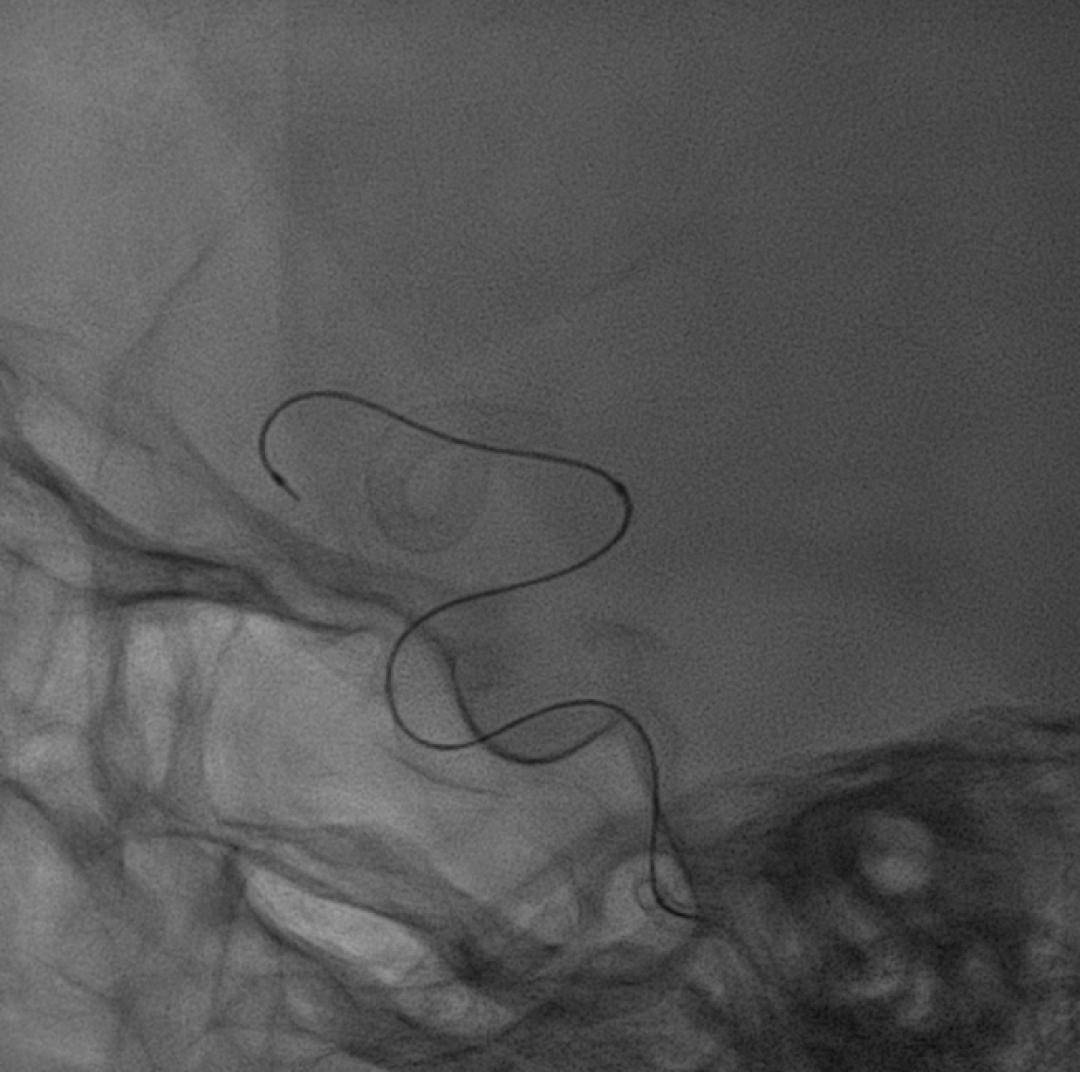

微导丝、微导管到位:

通路建立完成后,微导丝瘤内成袢,超选至大脑中动脉远端,支架微导管到位。

弹簧圈微导管到位。

Lattice远端释放:

Lattice输送到位后,透视下将支架远端定位于大脑中动脉M2段,回撤微导管原位释放支架,可见在支架头端机械球囊的辅助下,支架远端打开良好,头端导丝不位移。

继续释放支架至尾端,回撤微导管,支架自然打开贴壁满意,回撤球囊。

Vaso-CT显示支架打开及贴壁良好。